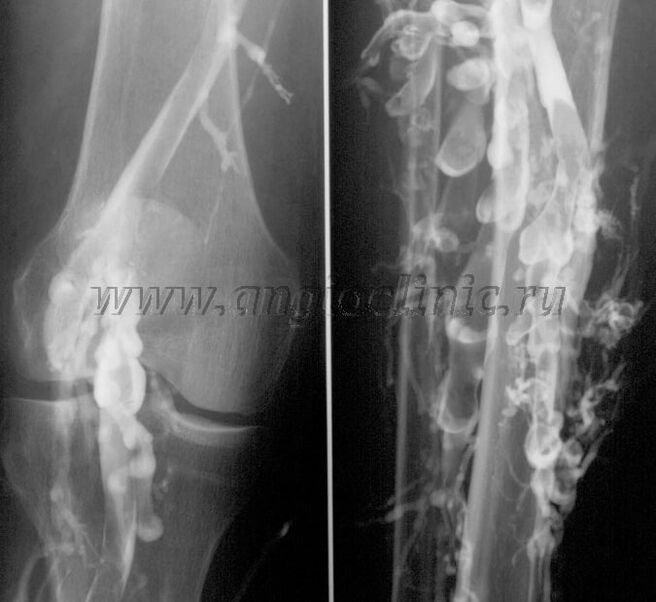

Kontrasta venogrāfija

Parasti pilnīgai vēnu patoloģijas diagnostikai pietiek ar ultraskaņas skenēšanu, taču atsevišķos gadījumos ir nepieciešams izpētīt dziļo un virspusējo vēnu sistēmas stāvokļa attiecības, īpaši varikozu vēnu un sekundāro vēnu recidīvu gadījumā.

Lai atrisinātu šīs problēmas, tiek izmantota kontrasta rentgena izmeklēšana. Tiek caurdurtas sapenveida vēnas un tiek ievadīts kontrasts. Rentgena aparāta monitorā tiek novērota kontrasta kustība, tiek veiktas visas nepieciešamās pārbaudes un projekcijas. Pašlaik venogrāfiju varikozām vēnām izmanto ļoti reti.